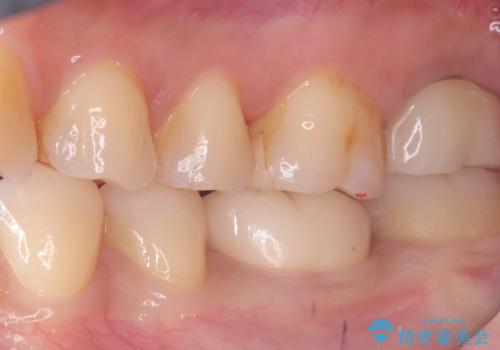

- 主訴:強く噛んだら歯がポロポロ欠けてきた。

左下6番目の歯の咬合面にプラスチックの材料が詰まっており、歯質がドーナツ状にしか残っていなかったため、歯質幅が比較的薄かった場所が欠けてしまったようでした。

今後の破折リスクを説明し、セラミッククラウンでのやり替えとなりました。

頬舌的レジンインレーが入っており、歯質幅の薄かった且つ強く咬合していた遠心側歯質が欠けてしまっていました。また新しい窩洞のインレーを入れても、近心側歯質の破折のリスクは抱えたままになることから、クラウンでの修復をおすすめし審美性・適合性のよいセラミッククラウンでのやり替えとなりました。